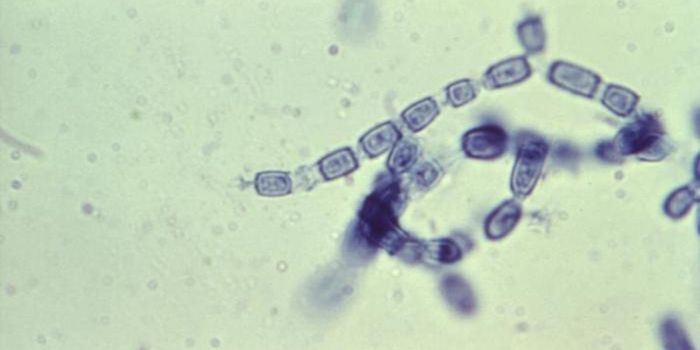

APR 19, 2022ImmunologyTuberculosis is caused by a bacterium, Mycobacterium tuberculosis, that is thought to have been around for about 150 mil ...